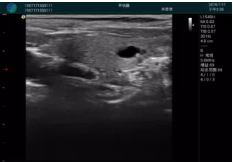

甲狀腺囊性結(jié)節(jié),囊壁鈣化,透聲好

甲狀腺囊性占位